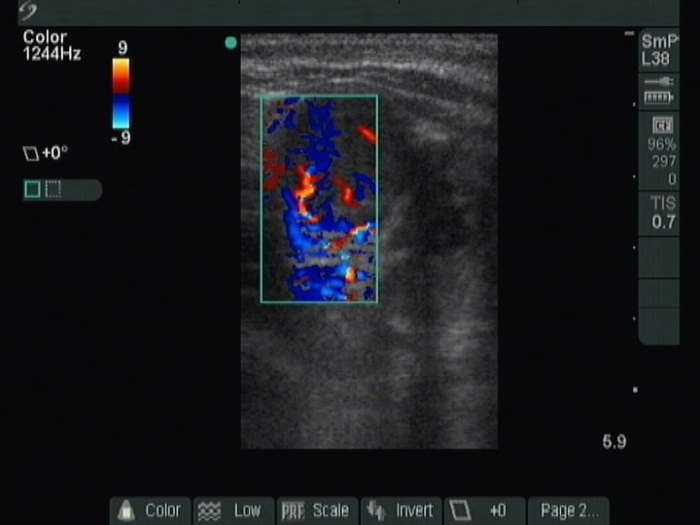

Lower third of the right lobe, transverse scan, color Doppler mode.